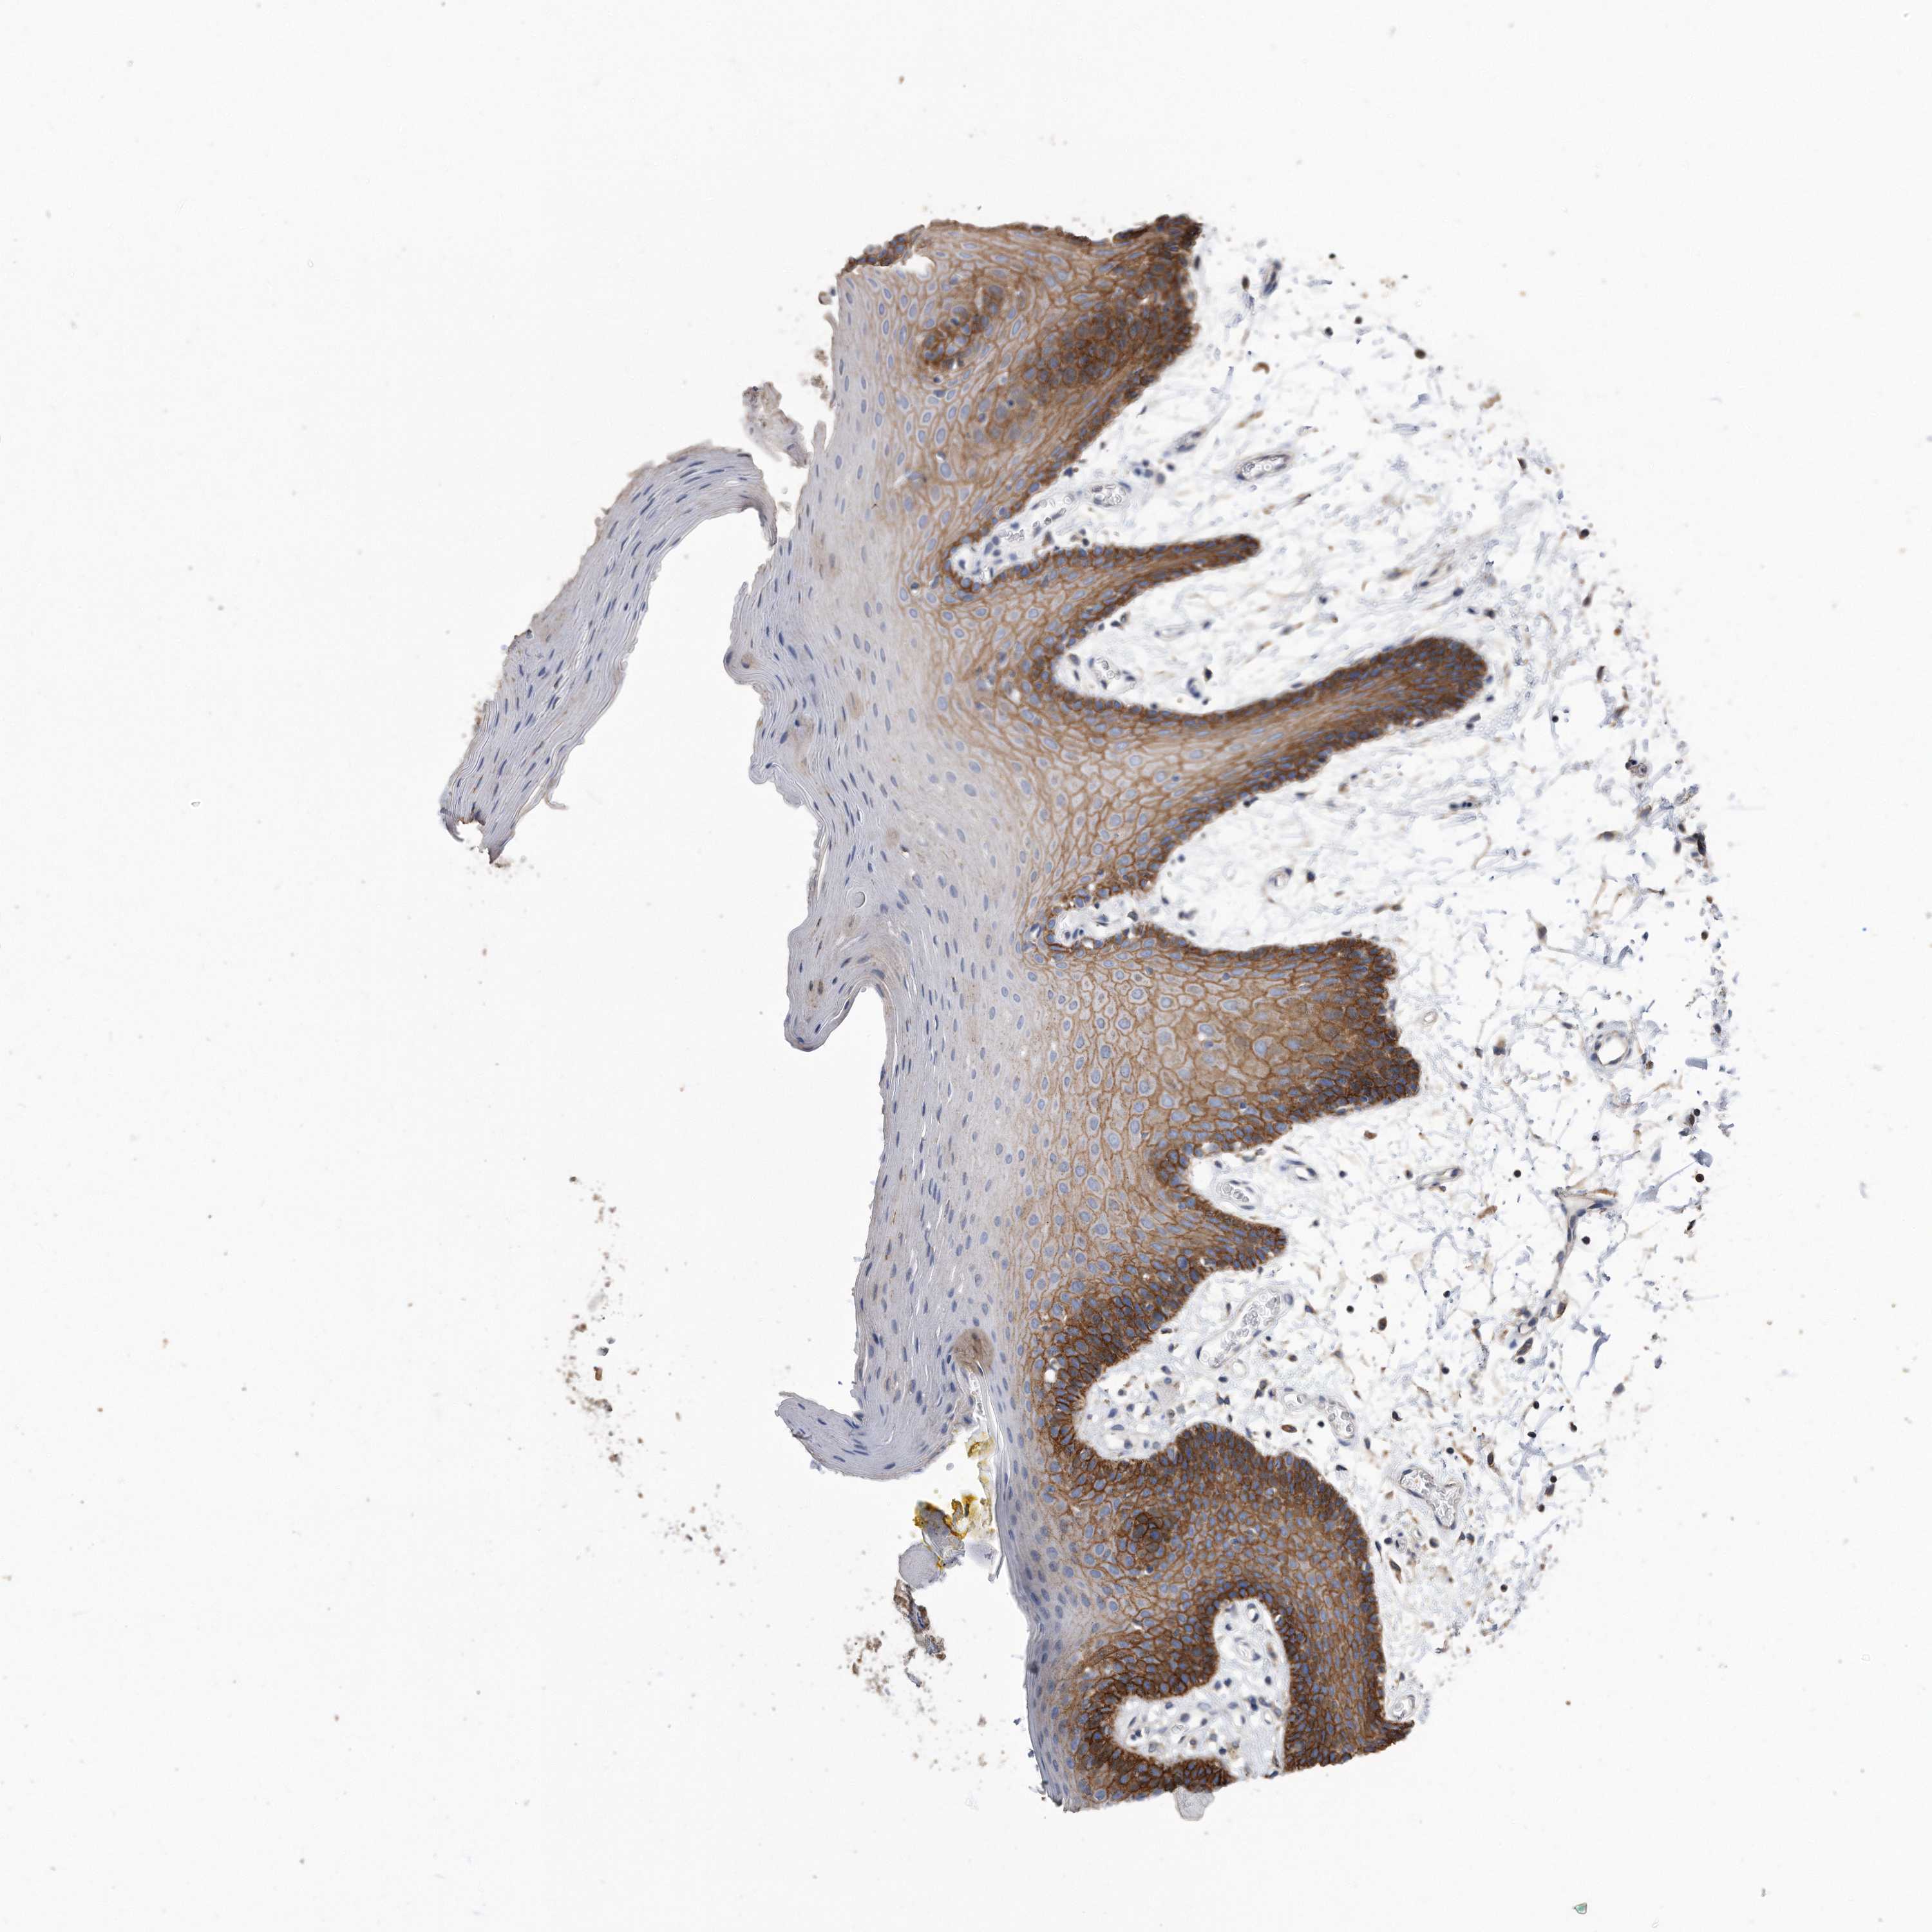

CDCP1